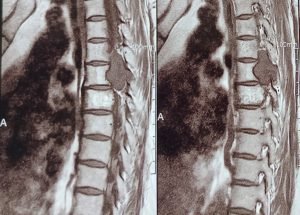

Expert spine services including minimally invasive surgery, pain management, and deformity correction.